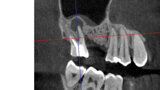

3D technologie v diagnostice a léčbě endodontických onemocnění